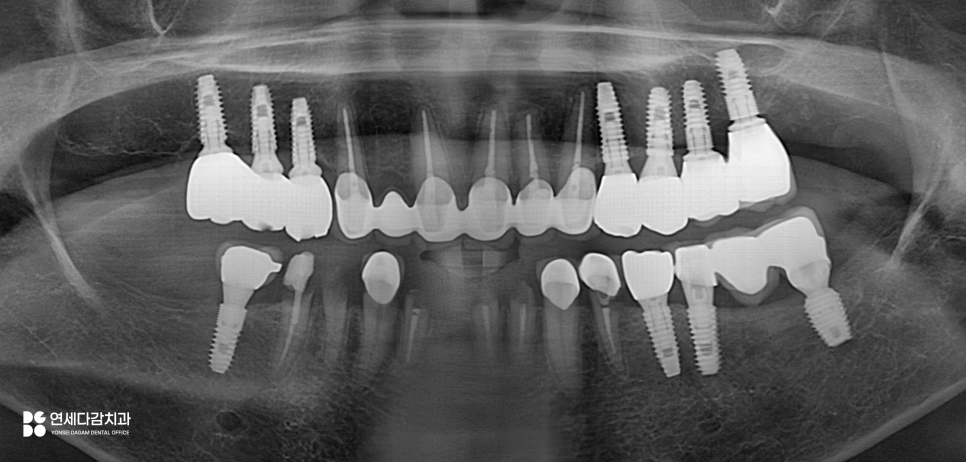

이런 경우, 임플란트를 고려할 수 있지만,

다수의 식립이 필요한 상황인 만큼

비용이 부담될 수 있습니다.

65세 이상의 환자시라면

보험 임플란트가 적용 가능하지만,

1인당 평생 2개까지만

급여 혜택이 주어지기 때문에

여러 개가 필요한 경우에는

결국 비급여 비용이 추가될 수밖에 없습니다.

이렇게 경제적 부담이 고려되는 분들은

부분 틀니(RPD)를 선택할 수 있습니다.

다만 오금역 치과 에서 한 가지 짚고 넘어가는 것은,

RPD는 남아 있는 자연치아에 걸쇠(클라스프)를 걸어

고정력을 확보하는 구조입니다.

앞서 오금역 치과 에서 보여드린 것처럼

기존 임플란트 보철물이 있어도

클라스프가 걸릴 수 있는 구조가 없으므로,

새로 제작하는 것이 필요합니다.